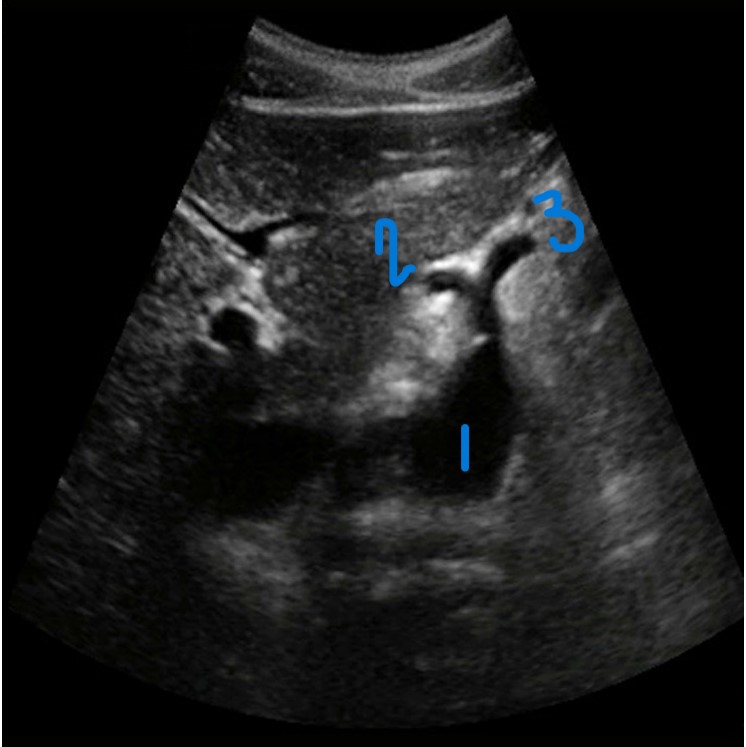

<p>In this Sagittal-Coronal plane, what is #1?</p>

In this Sagittal-Coronal plane, what is #1?

Right Renal Artery

<p>In this Sagittal-Coronal plane, what is #2?</p>

In this Sagittal-Coronal plane, what is #2?

Left Renal Artery

<p>In this Sagittal-Coronal plane, what is #3?</p>

In this Sagittal-Coronal plane, what is #3?

Aorta